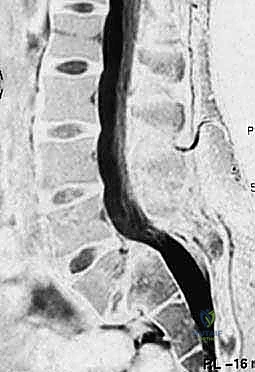

- التصوير بالرنين المغناطيسي (MRI): هو المعيار الذهبي لرؤية الأنسجة الرخوة. يوضح بدقة متناهية حالة الأقراص الغضروفية، ومقدار الاختناق في القناة الشوكية، والضغط الواقع على جذور الأعصاب.

الخطوة الأولى والأهم هي إزالة الضغط عن الحبل الشوكي والأعصاب. يتم ذلك من خلال استئصال الصفيحة الفقرية (Laminectomy) وإزالة الأربطة المتضخمة (Ligamentum Flavum) وأي أجزاء من الغضروف المنزلق تضغط على الأعصاب. يتم إجراء هذه الخطوة تحت الميكروسكوب الجراحي لضمان عدم المساس بالأغشية العصبية الرقيقة (Dura Mater). بمجرد تحرير الأعصاب، يزول سبب الألم الجذري (عرق النسا) فوراً.

في حالات الانزلاق عالي الدرجة، غالباً ما يتطلب الأمر دعماً إضافياً من الأمام (بين أجسام الفقرات). هنا يتألق الدكتور هطيف باستخدام تقنيات (PLIF - Posterior Lumbar Interbody Fusion) أو (TLIF - Transforaminal Lumbar Interbody Fusion).

في هذه التقنية، يتم استئصال القرص الغضروفي التالف بالكامل، ووضع قفص داعم (Cage) مصنوع من مادة الـ PEEK أو التيتانيوم، ومملوء بالطعوم العظمية، في مكان الغضروف. هذا الإجراء يعيد الارتفاع الطبيعي للفقرات، ويفتح مسارات الأعصاب بشكل ممتاز، ويوفر نسبة نجاح للدمج العظمي تقارب 100% لأنه يضع العظم في منطقة تتحمل ضغطاً ميكانيكياً عالياً مما يحفز نمو العظام.